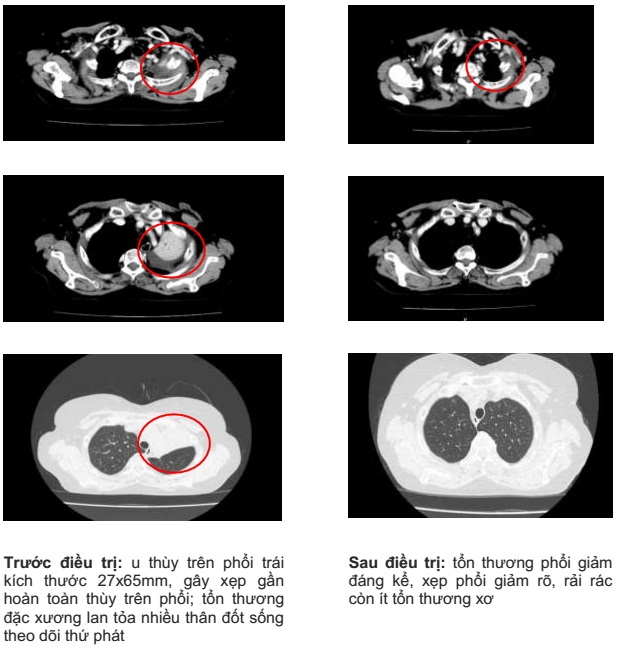

– Chụp cắt lớp vi tính lồng ngực: khối thùy trên phổi trái tỷ trọng tổ chức có phế quản chứa khí, có vôi hóa, dạng hình tam giác đỉnh quay về phía rốn phổi, đáy quay về ngoại vi kích thước 27x65mm, gây xẹp gần hoàn toàn thùy trên phổi; tổn thương đặc xương lan tỏa nhiều thân đốt sống theo dõi thứ phát.

Hình 1: Hình ảnh chụp cắt lớp vi tính lồng ngực: hình ảnh u thùy trên phổi trái, xẹp gần hoàn toàn thùy trên phổi trái

Chụp cắt lớp vi tính lồng ngực sau điều trị 3 tháng:

Hình 5: Hình ảnh chụp cắt lớp vi tính lồng ngực sau điều trị 3 tháng: tổn thương phổi giảm đáng kể, xẹp phổi giảm rõ, rải rác còn ít tổn thương xơ